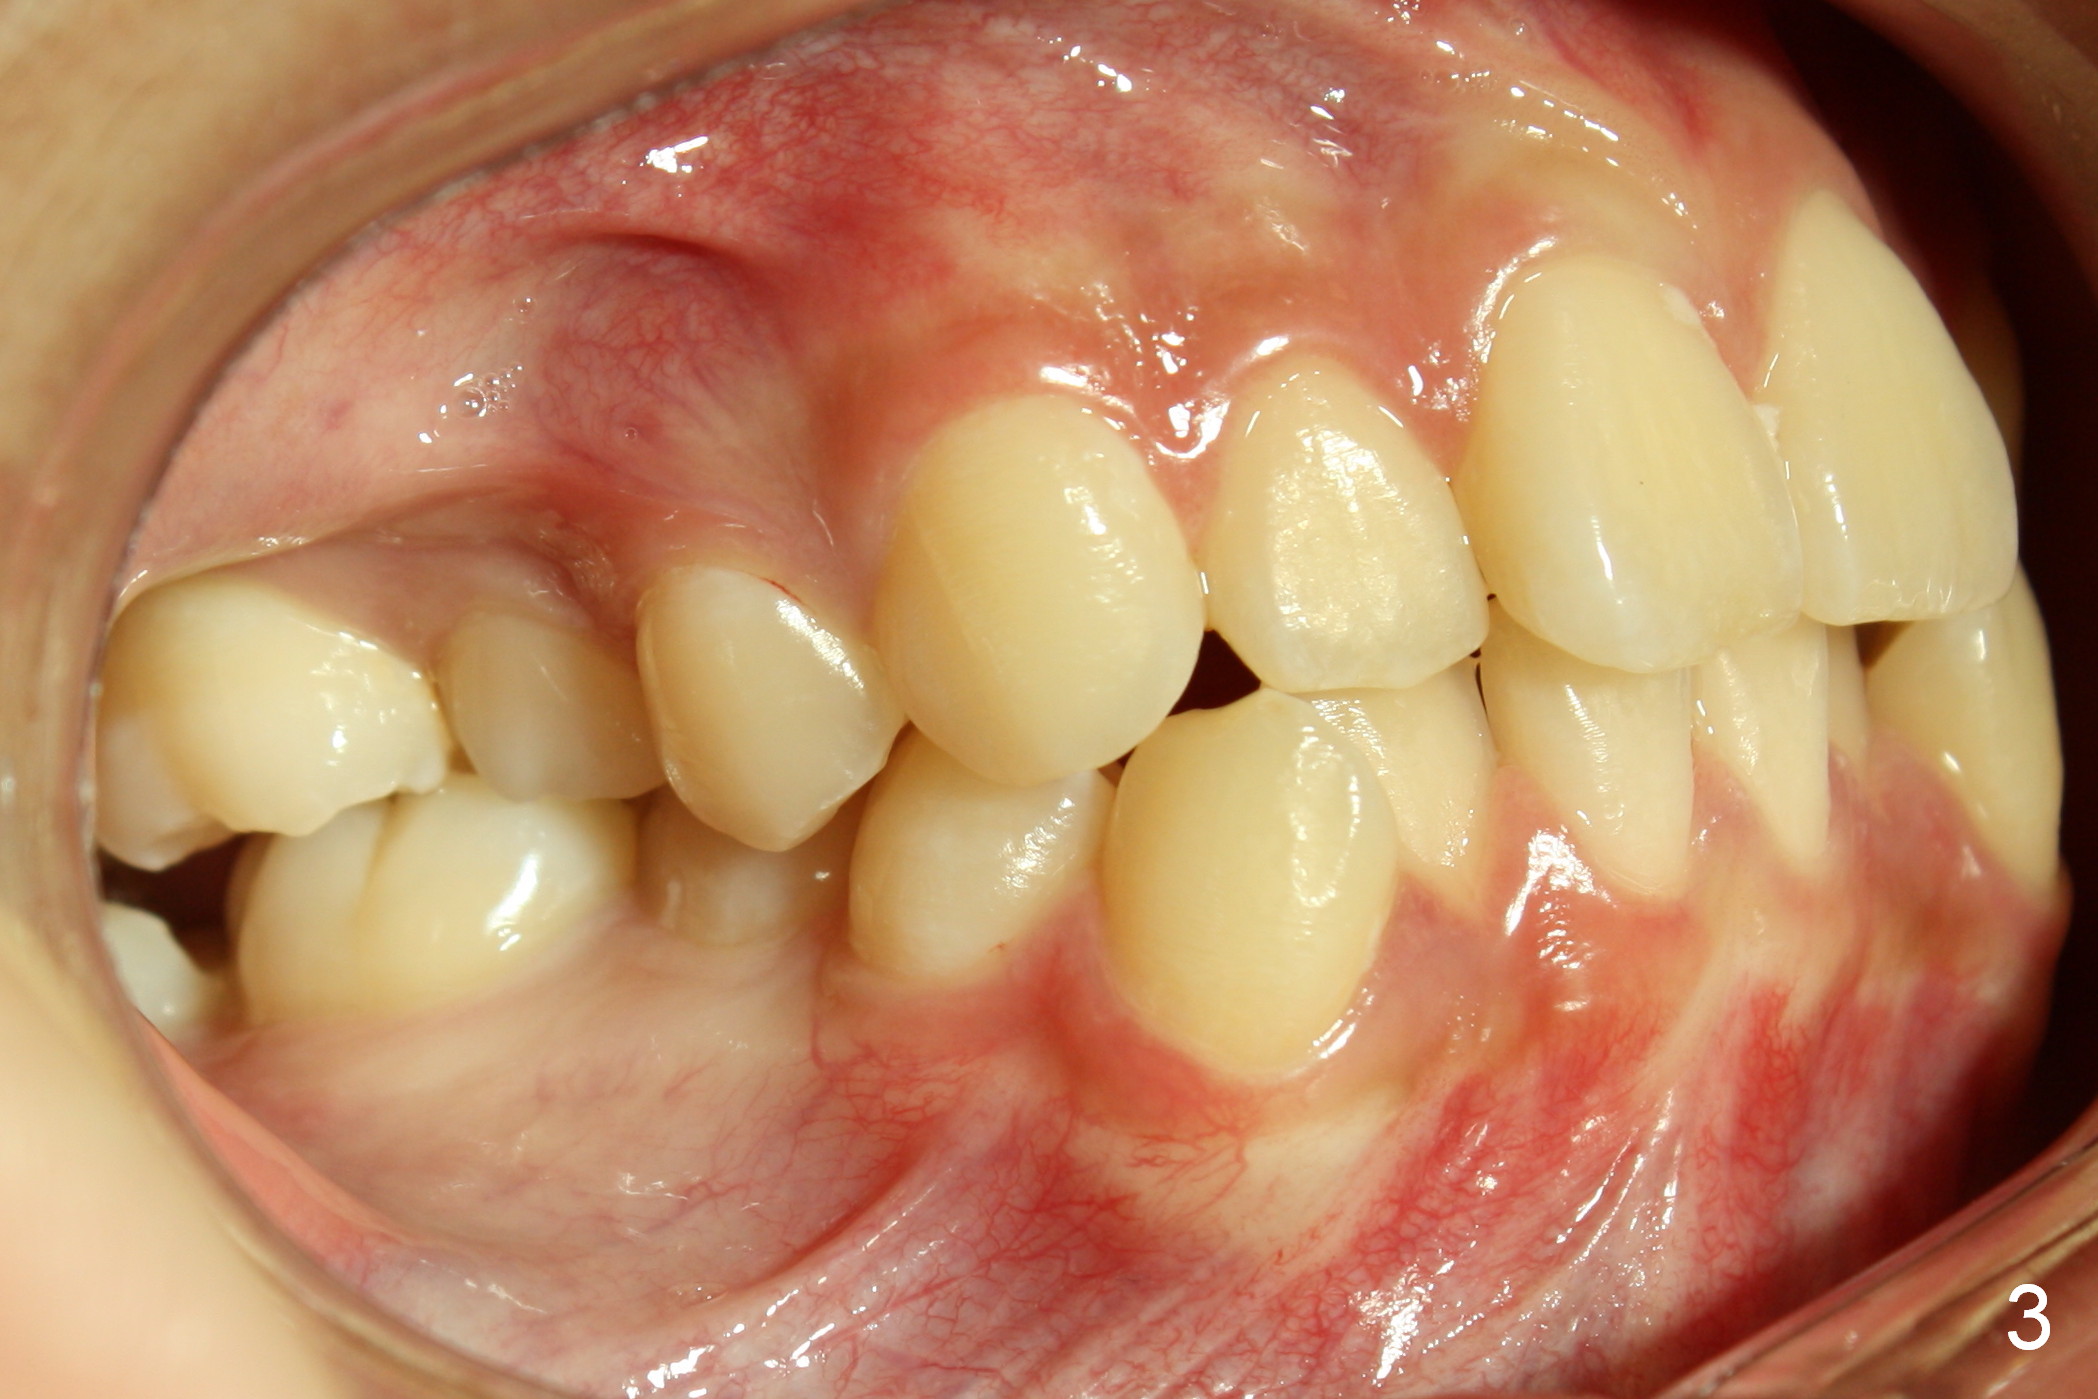

When taking photos for the lateral view of the occlusion (Fig.3, retract the corner mouth as back as possible using proper sized cheek retractors (single or double, child or adult) or a mouth mirror. The focus should be on the posterior teeth, showing interdigitation. That is move the camera to the side of the face.